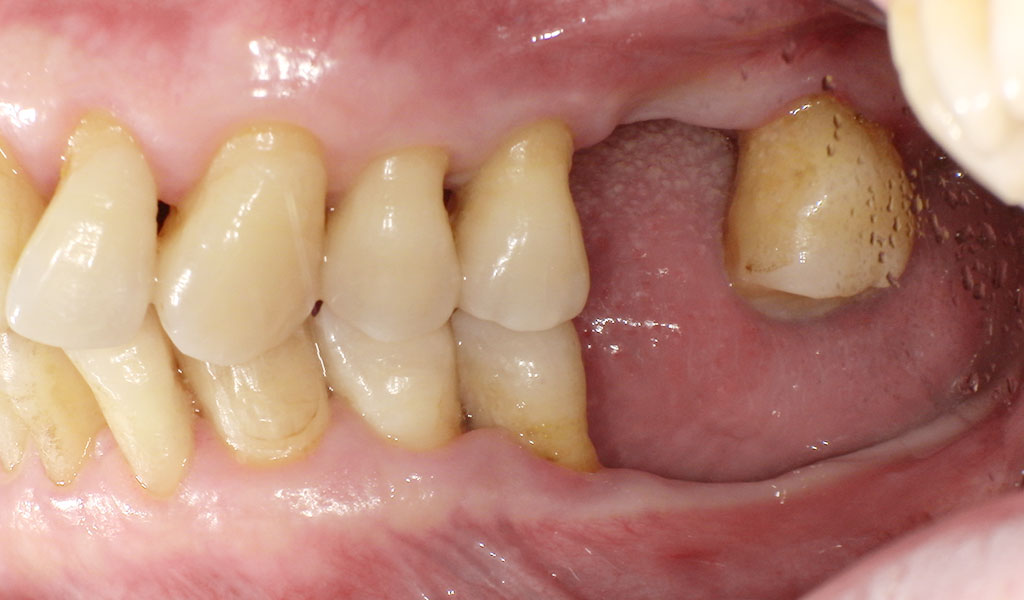

Before(右下5,6,7番)

60代男性・横浜市在住。歯周病により歯がぐらついていたため、当院にて左上6番、左下6,7番、右下5,6,7番を抜歯後、インプラント治療。人工歯はジルコニア人工歯。スクリューリテインにて固定しました。歯周病菌の数が多いため、歯周内科治療も実施しました。

通常手術にて、左上6番、左下6,7番、右下5,7番をの骨にインプラントを埋め込みました。